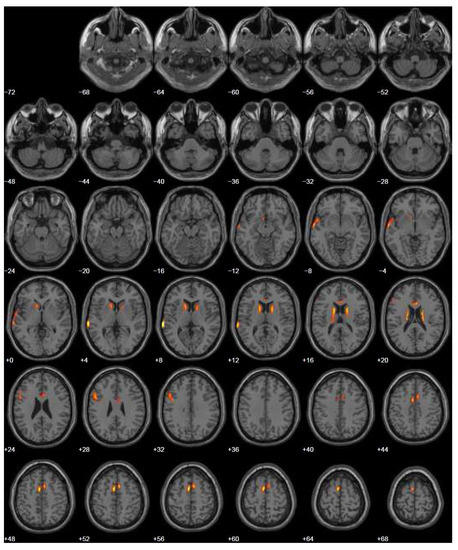

| 2012 | Neuropsychological assessment RMN | Negative Mild dilation of the sulci of the bilateral front parietal convexities |

| 2015 | Neurological assessment FDG-PET | Mild isolated motor speech disorder hypometabolism; more extensive involving left temporal gyrus, frontal gyrus bilaterally, cingulate, caudate, and thalamus bilaterally |

| 2021 | Neurological assessment Broad neuropsychological assessment | Mild cognitive impairment Sudden worsening of the condition of the patient |